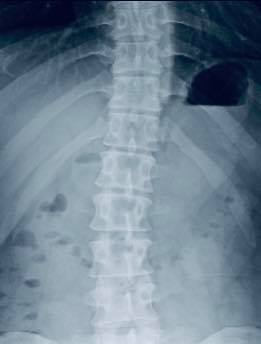

😂😂林先生在十年前出一場嚴重車禍導致胸椎跟頸椎受傷,X光片顯示頸椎前緣骨質增生、第二第三關節突增生、第六第七關節突卡壓 ,胸椎歪斜,最困擾症狀是上背悶痛,這幾年幾乎每周都會安排推拿,可以緩解胸悶的情況,但是一直沒有重大改善,狀況不好的時候也會引發背痛 ,來診前的這幾個月幾乎是每天都會痛,經過友人介紹來接受脊椎整合中醫微創療法

✳️診斷:胸椎小關節面沾黏合併頸椎神經根卡壓